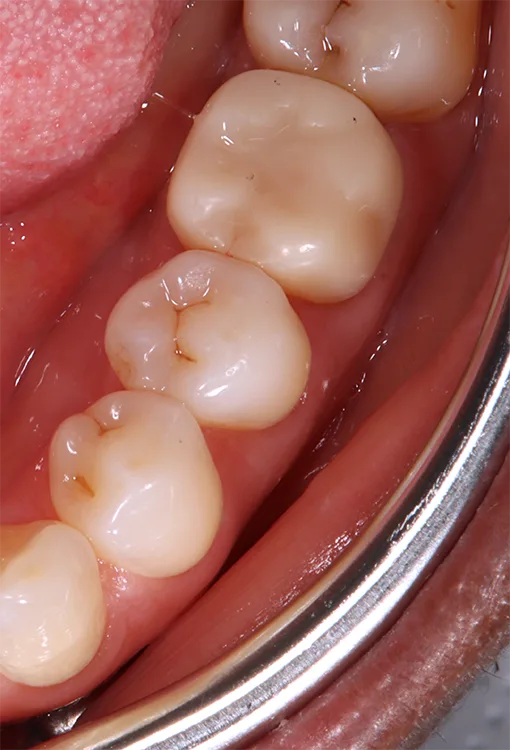

Die additive Fertigung von festsitzendem Zahnersatz kann in zwei weitere Gruppen eingeteilt werden: der provisorische Zahnersatz sowie der definitive Zahnersatz (Abb. 4a und b). Die Anforderungen für permanente Restaurationen sind deutlich höher, was erklärt, weshalb nicht jedes Komposit bzw. Material für definitive festsitzende Restaurationen zugelassen ist.

Die Hauptindikation der additiv gefertigten Restaurationen sind Einzelzahnrestaurationen wie Inlays, Onlays, Veneers, Teilkronen oder Vollkronen (Abb. 5). Aber auch der Einsatz als kurzspannige Brücke (provisorisch oder definitiv) ist möglich (Abb. 6). Der Einsatz additiv hergestellter Non-Prep-Langzeitprovisorien stellt eine außerordentliche Indikation dar und wird von den Herstellern nicht aufgeführt (Abb. 7).